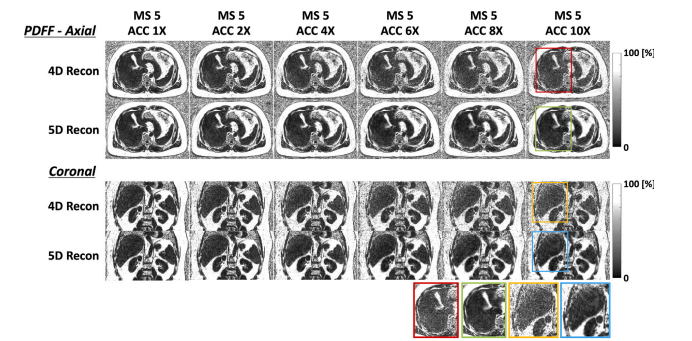

Fig. 6. Comparison of PDFF map quality. Axial and coronal views of 1X to 10X accelerated end-expiratory PDFF maps of a healthy volunteer with regular breathing from the4D reconstruction and the proposed 5D reconstruction are shown. Regions highlighted by colored bounding boxes in the 10X accelerated PDFF maps are enlarged and shownseparately, with matching colored bounding boxes

图6. 质子密度脂肪分数(PDFF)图质量的比较。图中展示了来自四维重建和本文所提出的五维重建的、一位正常呼吸的健康志愿者的呼气末质子密度脂肪分数图在1倍到10倍加速情况下的轴视图和冠状视图。在10倍加速的质子密度脂肪分数图中,由彩色边框突出显示的区域被放大并单独展示,且配有对应的彩色边框。